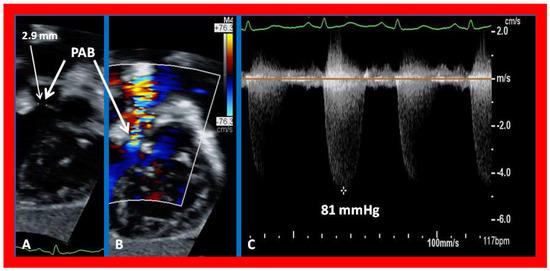

Figure 22. Selected echocardiographic video frames demonstrating pulmonary artery band (PAB) with narrow diameter of 2.9 mm by 2D (A) and by color flow (B) and a high gradient (81 mmHg) by continuous wave Doppler (C) are shown.

In patients who had banding of the PA, echo-Doppler studies should be scrutinized to demonstrate the banded PA diameter (Figure 22A,B and Figure 23A) and peak Doppler flow velocity across the banded PA (Figure 22C and Figure 23B); high Doppler velocity across the band (Figure 22C and Figure 23B) would suggest effective palliation. Low gradients and ineffective control of CHF may require tightening of the band; echo-Doppler evaluation is useful in making such an assessment.